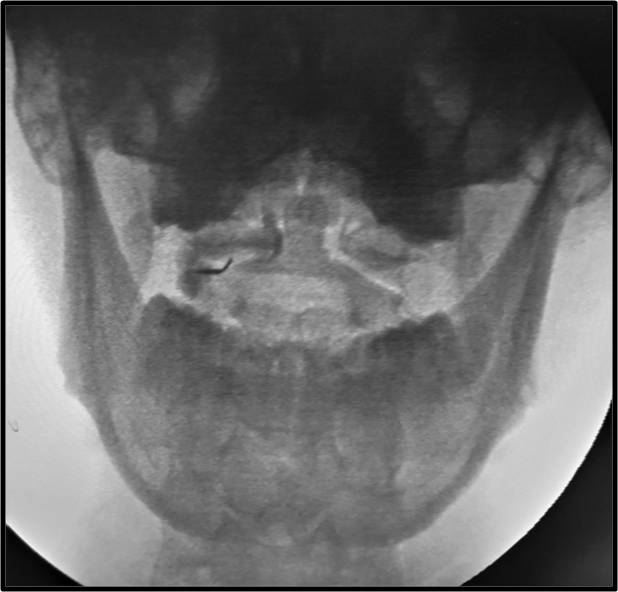

Τι είναι οι εγχύσεις στις αρθρώσεις της ανώτερης αυχενικής μοίρας της σπονδυλικής στήλης

Πρόκειται για την έγχυση μικρής ποσότητας στεροειδούς στην ατλαντοϊνιακή ή στην ατλαντοαξονική άρθρωση της ανώτερης αυχενικής μοίρας κάτω από ακτινοσκοπική καθοδήγηση. Η ανάπτυξη αρθρίτιδας ή ο τραυματισμός των αρθρώσεων αυτών μπορεί να αποτελεί πηγή χρόνιου σοβαρού πόνου στην αυχενοϊνιακή χώρα.